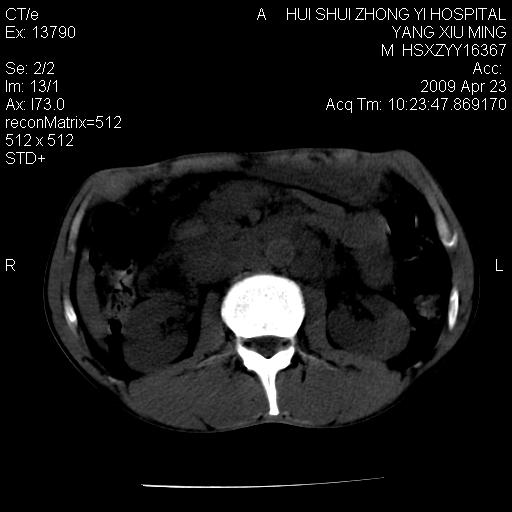

腹膜后淋巴结增大,转移、淋巴瘤?胰腺增大,胰腺炎?占位?颈部考虑增大淋巴结。建议腹部增强扫描。

缺少强化资料,暂考虑胰腺癌广泛转移.

连最基本的ct值都没有测        腹部的窗宽窗位太大了     影响诊断

黑!广泛淋巴结肿大不符合胰腺癌转移。胰腺周围淋巴结肿大致使胰腺看起来大。考虑淋巴瘤可能大。